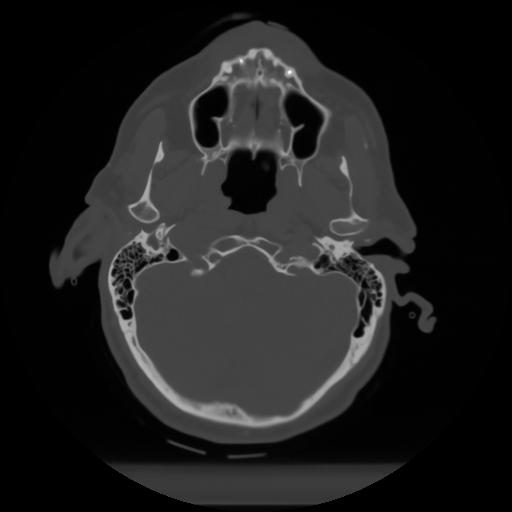

10 P.BLANDAS,,Axial,2.0,P.BLANDAS,,